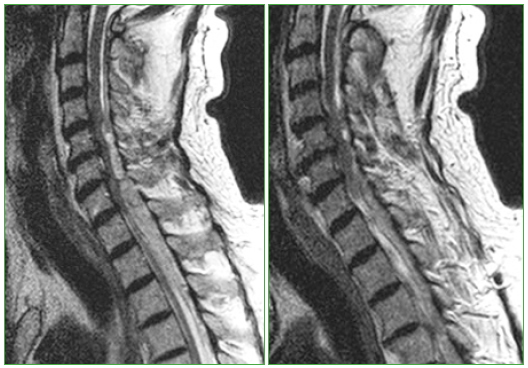

Antes se solicitan análisis de laboratorio completos, cuyos resultados están dentro del rango normal. Los resultados de los estudios de coagulación indican: tiempo de protrombina 21,2 s; tiempo de protrombina (cociente) 1,93; índice de Quick 39%; INR 1,91; tiempo de tromboplastina parcial activada 35,4 s y fibrinógeno 424 mg/dl. Todos los valores están dentro del rango de un paciente anticoagulado en el contexto del tratamiento con acenocumarol. La RM identifica, en el conducto espinal cervicodorsal, una colección heterogénea con extensión aproximada de C4 a T8, una longitud de 22 cm y con localización epidural-subdural posterior que comprime significativamente la médula (Figura). Por las características de señal y los antecedentes médicos del paciente, se correlaciona con una colección hemática. No fue posible precisar el origen del sangrado de vasos del conducto espinal, no se hallaron malformaciones vasculares ni otras causas. La compresión es más significativa desde C5 hasta T1, a esto contribuye la patología degenerativa discal con presencia de osteofitos y pequeñas protrusiones. La médula está comprimida en este segmento y muestra tenue alteración de señal en varios puntos, lo que indica probable contusión o edema.

Figura.

Resonancia magnética, en secuencia T2 de la región cervicodorsal. Se observa la colección hemática desde C4 hasta T8.